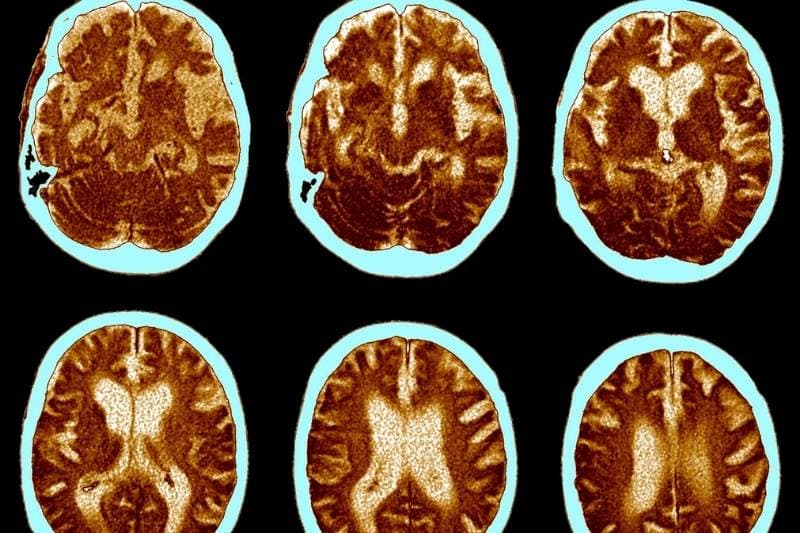

Scientists have found that the brain goes through severe changes in AD patients. The brain shrinks from its average size and toxic material keeps building up in different brain regions. A high number of protein deposits called Amyloid plaques and Tau tangles are specifically found to be deposited in the AD brain. These aggregated protein deposits cause previously healthy neurons to stop functioning, lose connections with other healthy neurons, and die. All these and many more changes cause brain to shrink.

AD can be categorized into mild, moderate and severe based on the severity of symptoms. Even with years of reaserch, the exact cause of the disease is not yet fully understood.The probable causes include a combination of genetic, exposure and lifestyle factors.